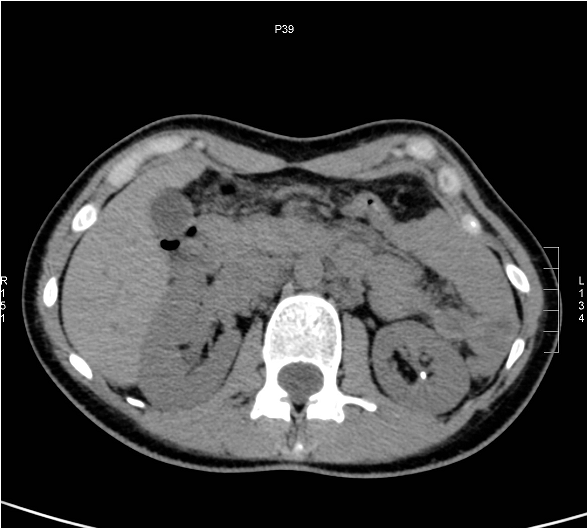

Image

Figure 7. CT image of extensive pyelonephritis involving the left kidney.

On the multiphase CT scan the affected parenchymal segment shows delayed contrast enhancement compared to its surroundings, and in the excretory phase it demonstrates a hypodense striated structure.

When abscess formation is suspected a CT scan must be performed. On the CT solitary or multiplex, circumscribed, round defects with a contrast enhancing wall are seen. Corresponding to the secondary perinephric stranding and to the extensive inflammation, abscesses can extend into the perinephric space. In such cases, depending on the severity of clinical symptoms, CT or US guided puncture can be attempted as a therapeutic intervention.